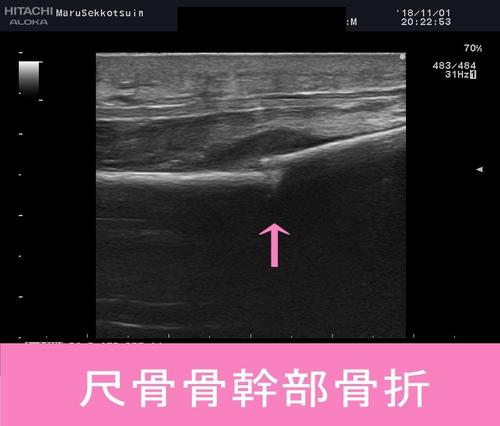

今日の「患者さまシリーズ」 59歳 男性 右腕で重たい袋を持ち上げようとした際、...